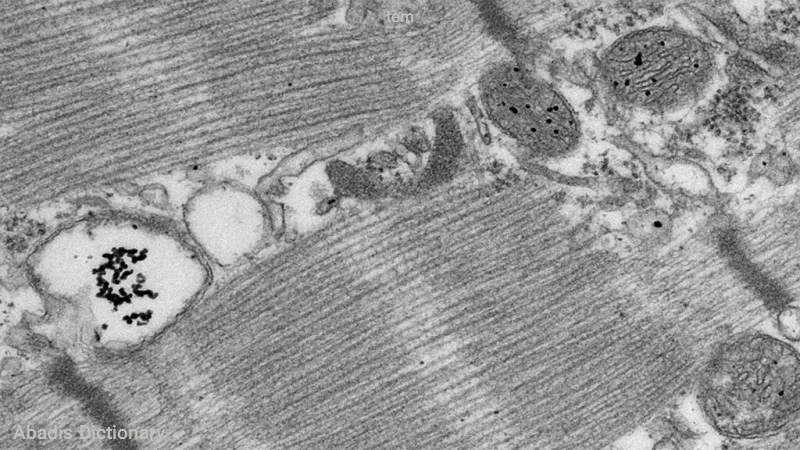

میکروسکوپ الکترونی عبوری یا TEM نوعی میکروسکوپ الکترونی است که قابلیت عکس برداری از ریزساختار مواد با بزرگنمایی ۱٬۰۰۰ تا ۱٬۰۰۰٬۰۰۰ برابر با قدرت تفکیکی در حد کوچک تر از ۱ نانومتر را دارد. میکروسکوپ الکترونی عبوری همچنین توانایی آنالیز عنصری، تعیین ساختار و جهت کریستالی اجزایی به کوچکی ۳۰ نانومتر را به صورت کیفی و کمی دارد.

میکروسکوپ الکترونی گذاره

میکروسکوپ الکترونی نگاره